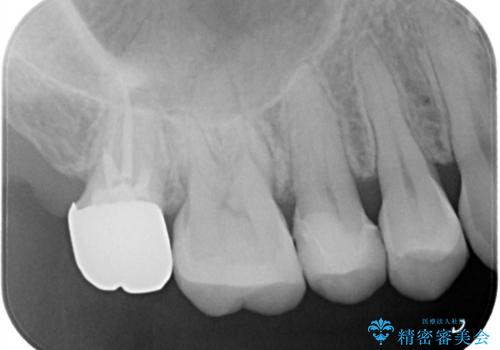

目立つ銀歯をセラミックに変えたい セラミックインレー

- 銀歯が気になるためやり替えたいとのことで来院されました。

セラミックインレーで治療を行いました。

口の中にチラつく銀歯は適合の良いセラミックインレーでやり替えることで綺麗にやり替えることができます。